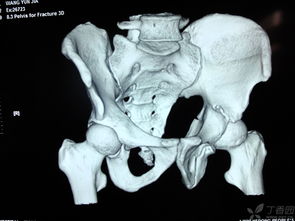

髖臼骨折,恥骨骨折,經(jīng)檢查無(wú)需住院,2回答者:lianghuanjie